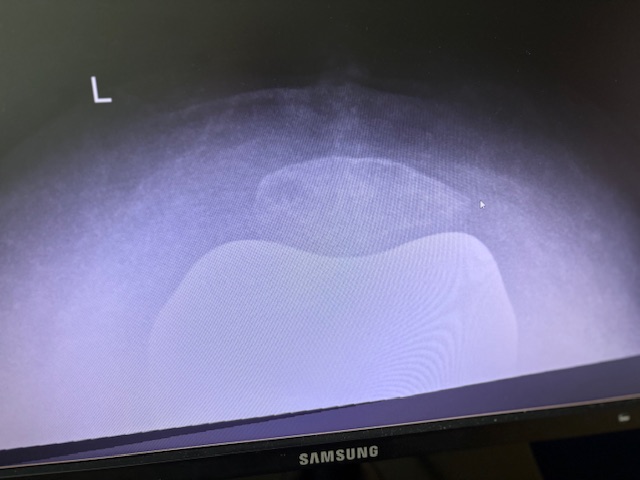

Η 80χρονη ασθενής παρουσίαζε έντονο πόνο και δυσκαμψία στο αριστερό γόνατο τα τελευταία χρόνια. Ο πόνος είχε επιδεινωθεί, επηρεάζοντας τη βάδιση και τη συνολική κινητικότητα, ενώ δυσκολευόταν ακόμα και σε απλές δραστηριότητες όπως το ανέβασμα σκαλοπατιών ή το περπάτημα σε μικρές αποστάσεις. Με την υπάρχουσα πρόθεση ισχίου στην αριστερή πλευρά η ασθενής ήταν αρκετά ευχαριστημένη. Ο ακτινολογικός και κλινικός έλεγχος ανέδειξε προχωρημένη οστεοαρθρίτιδα του αριστερού γόνατος, με πλήρη απώλεια του αρθρικού χόνδρου και παραμόρφωση του μηροκνημιαίου άξονα. Μετά από ανάλυση όλων των επιλογών, αποφασίστηκε η Ολική Αρθροπλαστική Γόνατος με Ρομποτική Υποβοήθηση, με στόχο την απόλυτη ακρίβεια στην τοποθέτηση των εμφυτευμάτων και την αποκατάσταση της φυσιολογικής μηχανικής του γόνατος.